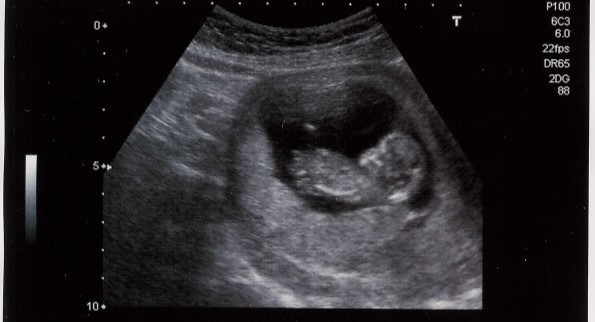

We hebben de afgelopen jaren in negentien ziekenhuizen in Nederland een grote studie gedaan. Uiteindelijk hebben 690 vrouwen die 32 weken of langer zwanger waren, en waarvan we wisten dat de baby’s relatief klein waren, aan het onderzoek meegedaan. Dat een baby klein is hoeft geen probleem te zijn, maar het kan ook zijn dat de placenta niet goed werkt en dat brengt gezondheidsrisico’s voor de baby met zich mee. Dat wilden we opsporen met een bepaalde Doppler-meting.

Vaak voelt een verloskundige aan de buik van een zwangere vrouw om te beoordelen hoe groot die is. Als die twijfelt of de grootte van de buik wel past bij de zwangerschapsduur kan je doorverwezen worden voor een groei-echo. Met een groei-echo wordt de buikomtrek, een bot in het bovenbeen en de hoofdomtrek van de baby gemeten en op basis daarvan wordt de groei berekend. We vinden een baby kleiner dan verwacht als die groei onder het tiende percentiel is. Daarmee bedoelen we dat deze baby’s horen bij de kleinste tien procent van alle ongeboren baby’s. Die baby’s worden dan extra in de gaten gehouden tijdens de zwangerschap en ook worden zij vaak vroeger geboren door middel van een inleiding. Uit de groei-echo blijkt alleen vaak niet of er daadwerkelijk sprake is van een niet-goed functionerende placenta en extra’s risico of dat de baby klein maar gezond is.

De Doppler-meting is een meting die tijdens de zwangerschapsecho uitgevoerd kan worden. Met de echo zoek je dan het bloedvat in de navelstreng op en kan je daar de weerstand in meten. Dit zegt iets over de doorbloeding van de placenta. Daarna wordt de weerstand in een vat in het hoofd van de baby gemeten. Als de placenta het minder goed doet, zet de baby dit vat in de hersenen verder open, zodat de bloedtoevoer naar de hersenen verbeterd wordt. Zo beschermd de baby de hersenen, het belangrijkste orgaan, voor het gebrek aan voedingstoffen en zuurstof door een niet goed werkende placenta. Een Doppler-meting kan dat registeren en vertelt ons of een placenta wel of niet goed werkt en of een baby dus een hoger risico heeft op problemen zoals zuurstoftekort of in ernstige gevallen zelfs overlijden.